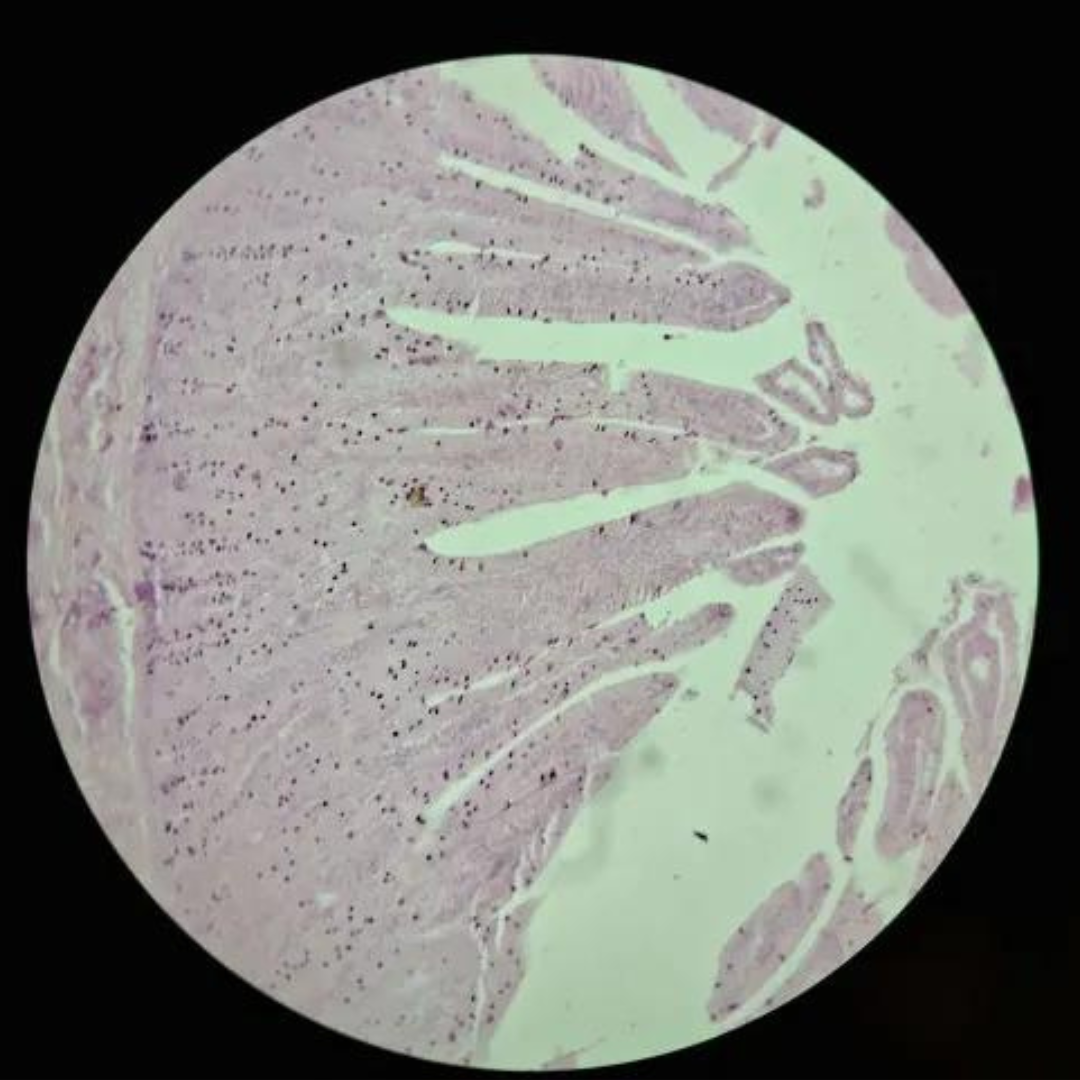

Jejunum

Duodenum

Jejunum

Jejunum

Jejunum

Jejunum

Jejunum

Jejunum